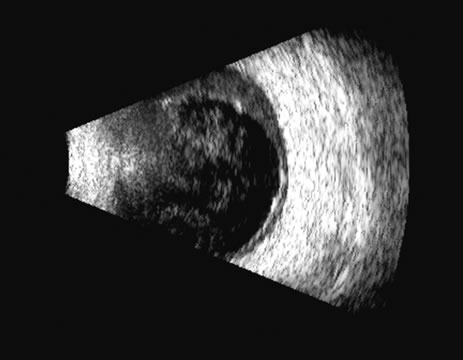

There are several tumors that invade the vitreous or the vitreous space. In children, retinoblastoma can seed the vitreous; in adults, reticulum cell sarcoma can cause vitreous clouding but is nondiscernible from other forms of debris. A very high percentage of retinoblastomas contain calcium, which is very reflective (Fig. 20). Malignant melanoma, hemangioma, metastatic carcinoma, and subretinal hemorrhage can all present with elevated convex lesions that protrude or extend into the vitreous space and are the four most commonly seen posterior segment tumors. Anteriorly, medulloepithelioma (diktyoma) and melanocytoma or ciliary body cysts can also protrude into the vitreous. The differentiation of these tumors has been well described with conventional combined B- and A-scan ultrasound techniques2 and standardized A-scan echography,28 as well as more modern spectral analysis techniques. These all provide excellent means of differentiating solid from cystic lesions, but differentiation between diktyoma (medulloepithelioma), melanocytoma, and melanoma is not possible with A-scan or B-scan.

Fig. 20. An eye filled with a retinoblastoma, which has considerable calcium deposits that produce a very reflective, high-amplitude echogenic structure (arrows).